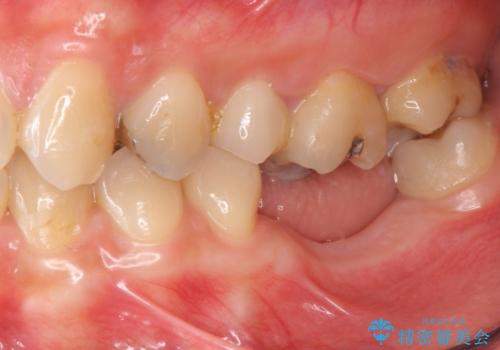

- 他院で抜歯後放置してしまった左下の奥歯の機能・見た目の回復を希望され来院されました。

放置したことによる影響か骨が吸収し、インプラント周囲に十分な骨が確保できないような状況であったため骨造成を併用したインプラント治療を計画します。